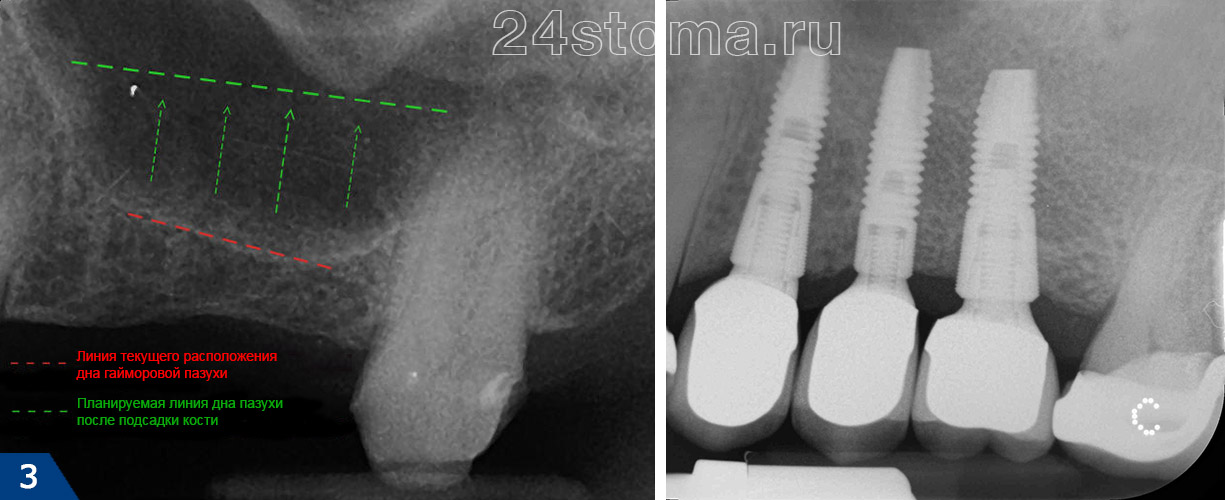

Исследование на рентгене после имплантации зубов

Раздел: Снимки-откровения